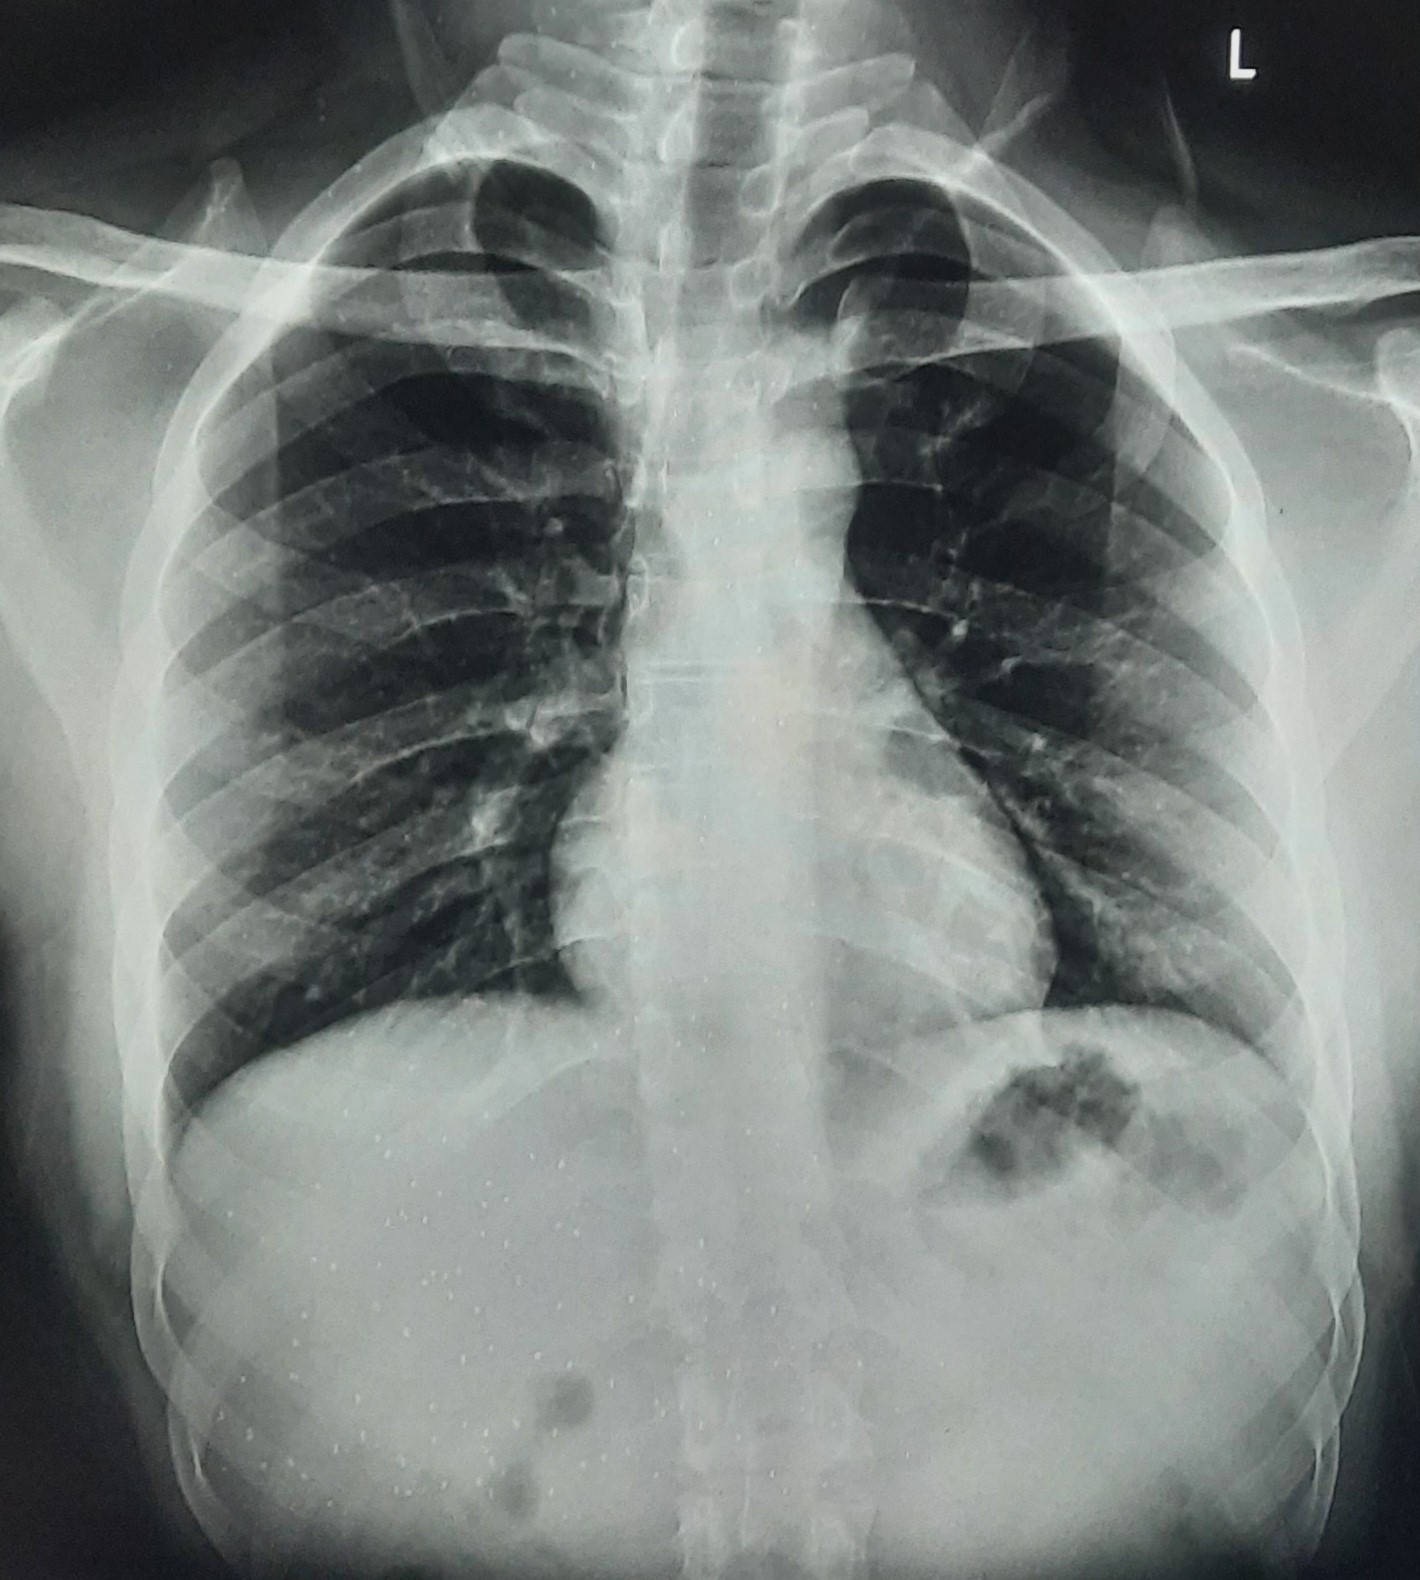

| 350 | IGGMC, Nagpur, Nagpur | P2 | 29-4122 | Pravin Thaware | Consent taken on Paper | 32 Yrs. |

Provisional Diag : Pre-Employment Medical fitness

Final Diag : CxR No Finding (Medical Fitness) |

Pure Normal Case (Cases with no complaint, NAD or medical fitness cases) | NODULAR OPACITIES SEEN IN BILATERAL HILAR REGION | No abnormality visible on x-ray |